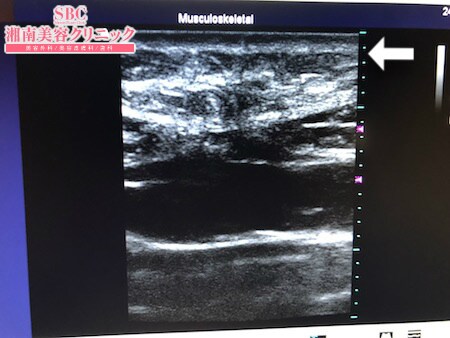

No.228703【脂肪吸引】【動画あり】湘南美容外科脂肪吸引最高責任者である竹田先生による脂肪吸引のフォトギャラリー!他院の再手術!脂肪吸引が難しいおなかの取り残された皮下脂肪を根こそぐ!術中3Dタッチビュー・上腹部

診察の結果、確かに皮下脂肪の取り残しを

認めましたので

今回はその再手術をすることに。

おなかの皮下脂肪の吸引は

非常に難しいと思います。

特に今回の患者様の皮下脂肪は

とにかく線維質で硬い。